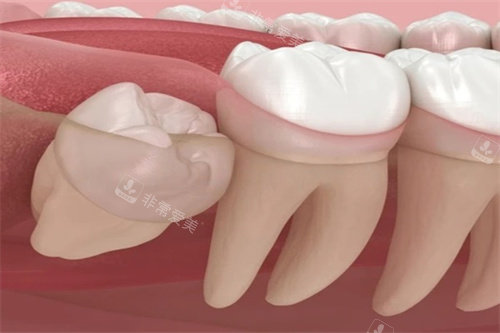

2. 阻生智齿拔除(中度难度):

阻生智齿多呈倾斜或水平生长,部分萌出暴露牙龈,可能压迫邻牙或形成盲袋,拔除需切开牙龈、分块取出。

垂直阻生智齿拔除:600-900元起

水平阻生智齿拔除:800-1500元起

部分骨埋伏阻生智齿拔除:1239-1800元起

这类智齿拔除耗时30-40分钟左右,术后需简单缝合,价格差异主要源于阻生角度和对邻牙的压迫程度,水平阻生因需分割牙齿,价格高于垂直阻生。